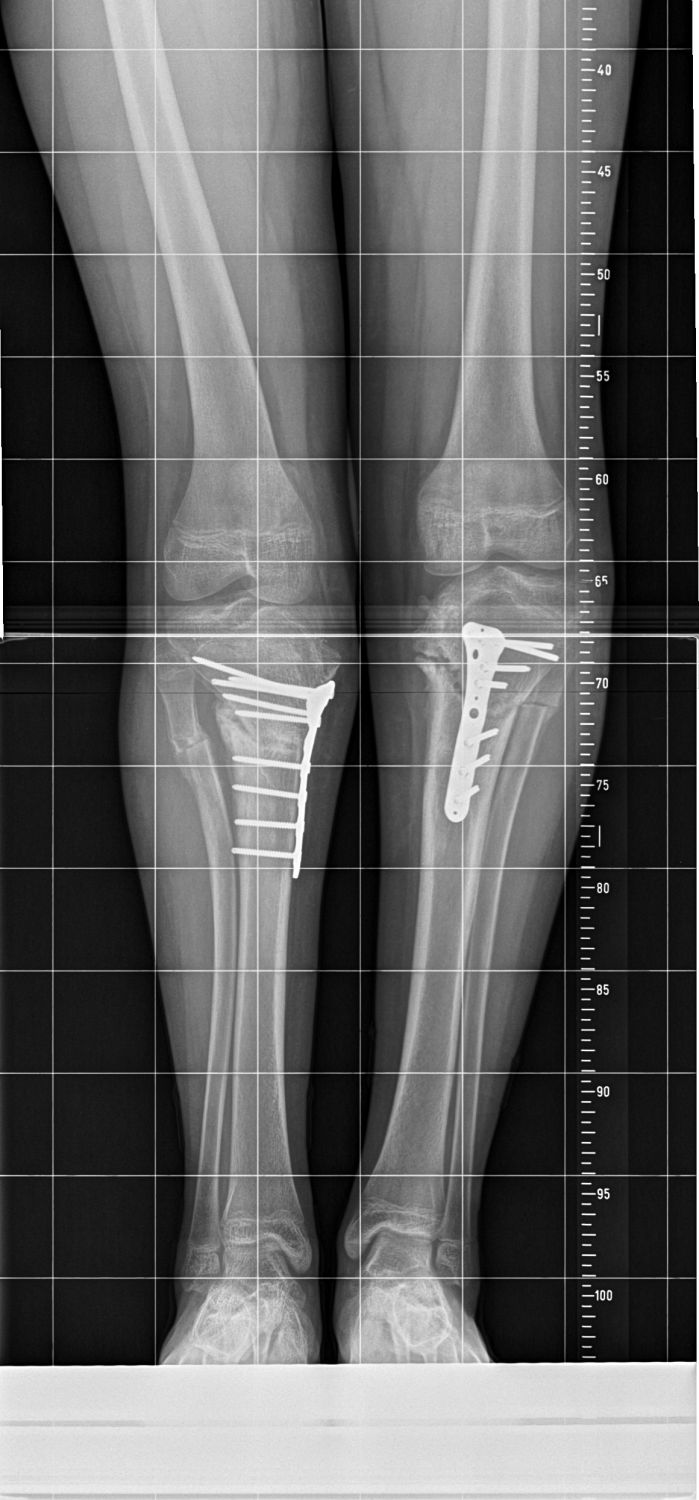

Maria leidet an Morbus Blount, einer knöchernen Wachstumsstörung im Schienbein. Betroffene entwickeln O-Beine – bei Maria sind diese extrem ausgeprägt.

Ohne Behandlung könnte das Mädchen irgendwann nicht mehr laufen. 2019 begradigten Chefärztin Christine Bollmann und ihr Team zunächst das rechte Bein und stabilisierten es mit einer Spezialplatte. Noch im gleichen Jahr folgte das linke Bein. „Wir hatten gehofft, dass sich die Wachstumsfuge erholt und Marias Beine gerade weiterwachsen. Dies hat sich leider nicht bestätigt“, so Dr. Bollmann. Mit fortschreitendem Wachstum wurden Marias Beine wieder krumm. „Hätten wir damals noch abgewartet, könnte sie heute gar nicht mehr laufen, dann wären die Knie längst kaputt.“

Diesen Herbst wurden Marias Unterschenkel erneut begradigt. In einer ersten Operation wurden eine komplexe Achskorrektur des Unterschenkels und eine Stabilisierung des Knochens durch eine Platte vorgenommen. Die Wachstumsfuge im Unterschenkel wurde dabei zusätzlich verödet werden, damit die Beine nicht noch einmal schief werden.

In der folgenden Operation wurde das zweite Bein ebenfalls korrigiert. Nun war Marie erneut im Marienstift: Zur Mobilisation und Orthesenanpassung. Zwischen den Behandlungsphasen bleibt Maria im Friedensdorf, fernab der Heimat. „Bei guter Heilung und Mobilisation kann sie im Frühjahr 2024 nach Hause“, sagen Dr. med. Jens Raabe und Dr. med. Daniel Herz, Oberärzte an der Klinik für Kinderorthopädie des Marienstifts.